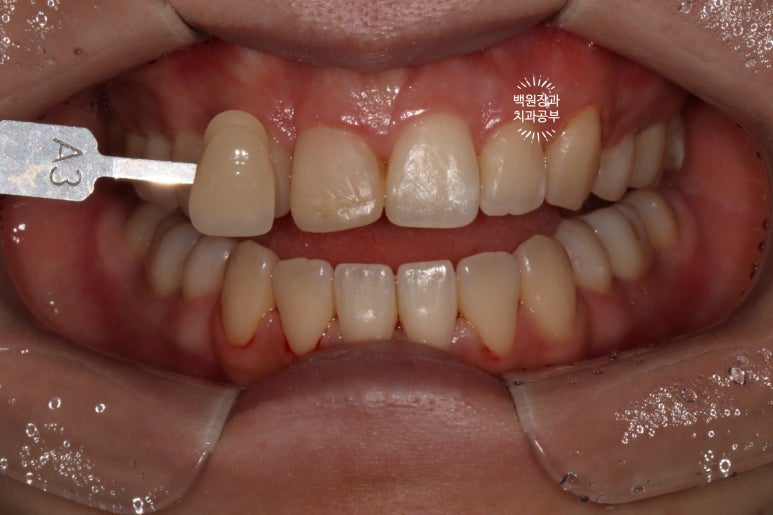

미백치료를 먼저 했습니다.

치아미백을 하여 전반적인 색조 개선을 합니다.

미백치료의 시작은 스케일링입니다!

깨끗한 상태로 만들어드려야 미백 결과도 더 예쁘게 보인다구요~

중요한 것은 우리가 치료할 예정인 치아는 이미 레진으로 치료가 되어있고, 레진은 미백으로 밝아지지 않는다는 것입니다.

전반적으로 A2.5~A3 shade를 갖던 치아들이, 2시간 정도 전문가 치아미백을 받고 나서

B1보다도 더 밝아졌답니다.

전반적으로 색조가 whitish하게 개선되었네요!